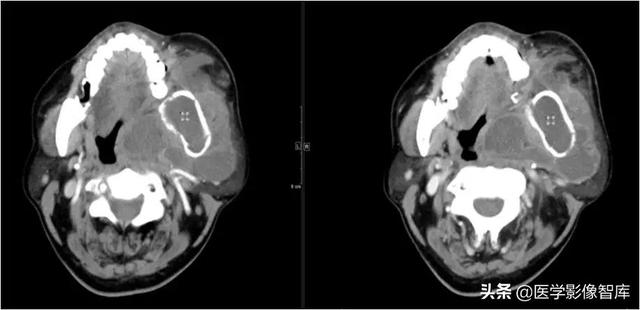

眶下间隙、颊间隙、咀嚼肌间隙、咽旁间隙

男,61岁,左侧面颊部、颌下、颏下肿胀15天,表面皮肤稍红,皮温不高,未扪及明显波动感。

角化囊肿并感染。